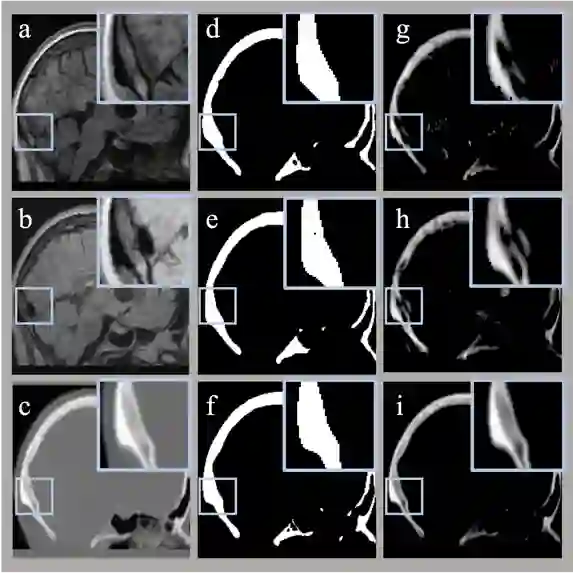

Image segmentation, real-value prediction, and cross-modal translation are critical challenges in medical imaging. In this study, we propose a versatile multi-task neural network framework, based on an enhanced Transformer U-Net architecture, capable of simultaneously, selectively, and adaptively addressing these medical image tasks. Validation is performed on a public repository of human brain MR and CT images. We decompose the traditional problem of synthesizing CT images into distinct subtasks, which include skull segmentation, Hounsfield unit (HU) value prediction, and image sequential reconstruction. To enhance the framework's versatility in handling multi-modal data, we expand the model with multiple image channels. Comparisons between synthesized CT images derived from T1-weighted and T2-Flair images were conducted, evaluating the model's capability to integrate multi-modal information from both morphological and pixel value perspectives.